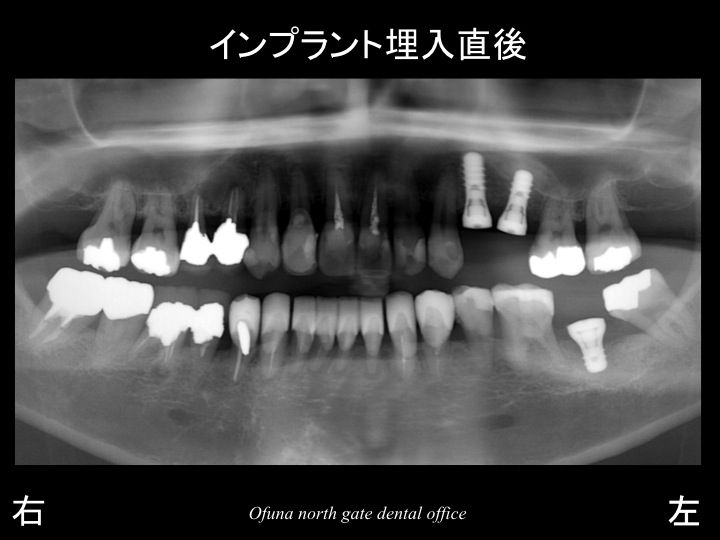

詳細は、後で解説しますが、先にインプラント埋入後のレントゲンになります。

インプラント埋入後のレントゲン拡大を見てみましょう!

奥のインプラントの尖端に見える白っぽくなっているのがソケットリフト法 によって入れられた人工骨です。

このままでは、わかりづらいので、

骨の状態を赤線、

もともとの上顎洞の状態を緑線、

現在の上顎洞の位置を黄色線で表示します。

人工骨によって上顎洞が上方に押し上げられたのが分かるかと思います。

さらに治療前後の比較を見てみましょう!

こう見ると分かりやすいと思います。